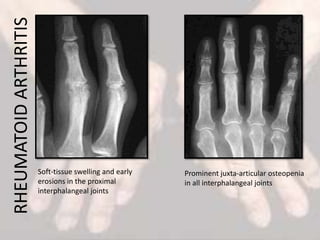

Soft-tissue swelling and early

erosions in the proximal

interphalangeal joints

Prominent juxta-articular osteopenia

in all interphalangeal joints

RHEUMATOIDARTHRITIS